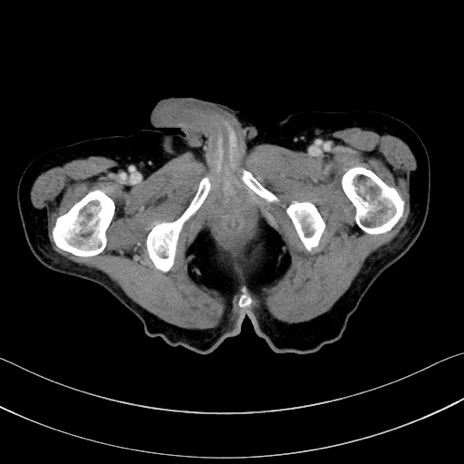

症例28(横断像)

【症例】60歳代男性

【主訴】嘔吐

【現病歴】胃癌にて胃全摘後。食思不振が悪化し、夜中に嘔吐することがある。

【既往歴】胃癌、胃全摘、脾摘、胆摘後

【データ】WBC 5900、CRP 10.56